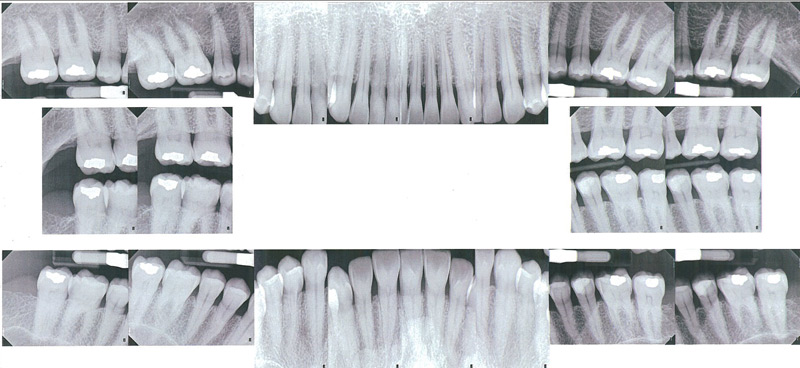

Full Mouth Periapicals

The most complete periodontal x-ray exam is the full mouth periapical exam. Each film shows the entire tooth and surrounding bone, in detail, and allows the periodontist to see subtle change occurring in the bone support. Root canal problems around the root tips are also easily seen. Generally 16-18 films are exposed. It is recommended that patients who have had moderate or advanced periodontal disease have full periapical x-rays every three years. In addition, bitewings are suggested every 6-12 months to check for decay.